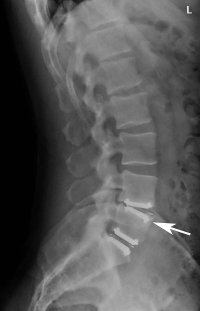

The artificial disc replacement (ADR) for lumbar spine has been designed to allow some motion of the defective segment by replacing the damaged disc with this implant. This theoretically reduces some stress on the segment above to prevent further degeneration of this superior segment. The artificial disc however has some significant deficiencies that need to be discussed.

First- the artificial disc does not mimic the behavior of a normal lumbar disc. The normal lumbar disc allows motion but is restrained at endpoint of motion. That is- the normal disc acts like a bushing where motion at the extreme limits is dampened by the fibers of the annulus. The artificial disc does not have this constraint and this puts more stress on the facets than the normal disc would. Also, the artificial disc does not have shock absorption capabilities like the normal disc does. This rigidity in compression can allow increased wear and can cause back pain after implantation.

Third is that over time, if the patient becomes osteoporotic, the disc can erode into the endplate of the vertebra which causes increased pain and dysfunction of this segment.

Finally- the lack of “normal” motion of the artificial disc can wear out the facets in back which will lead to back pain and fusion of the segment. Also- this motion can allow bone spurs to occur which could lead to nerve root compression.